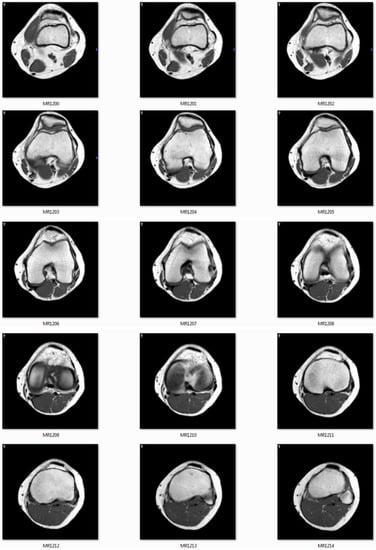

The CT/MRI of 32/64/128 slides must be provided to use as input images. Figure 11 shows the MRI slides of human knee.

Figure 11.

The image slides used as input data.